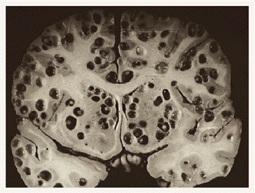

http://i.imgur.com/O4dlwUi.jpg

(管理人注:画像閲覧注意)

http://i.imgur.com/XM8HPbJ.jpg

蓮コラ並み

>>51>>52

オワリダナ

>>51-52

背筋ぞわっとした今までで最悪のグロ画像

これマジなら>>1ヤバくね

まあこんな状態だったらとっくに死んでるだろうし手術なんて無駄だろうけど

こうならないうちにとっとと取っちまった方がいいさ

早く見つかってよかったよ

Title : ↑

多数の穴があいた脳みその画像ですよ。51と大して変わらないです。グロさは…まぁそれなりに…